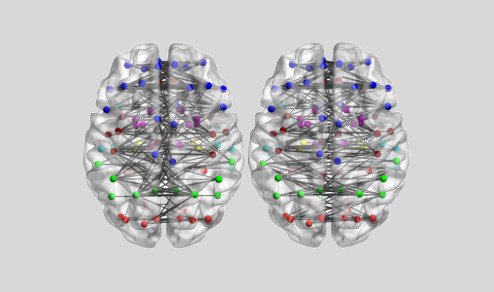

Este año, los científicos han descubierto que al ‘alternar’ las frecuencias en un patrón fractal, se consigue emular el ciclo de la naturaleza al crear nuevas conexiones neuronales, estimulando con éxito la corteza prefrontal.

Mediante una fusión de los efectos de sincronización hemisferial y neuronal.

Sincronización Hemisferial + Neuronal = Activación Prefrontal

Gracias a su tecnología de diferencia interaural, se logra sincronización hemisferial.

Sincronizando tus ondas cerebrales entre hemisferios para liberar tu máximo potencial cognitivo.

La segunda capa de la frecuencia híbrida, impulsada por HybridWave™.

Utiliza pulsos isocrónicos para inducir un estado de sincronización neuronal profunda.

Afinando el ritmo y la vibración de la actividad eléctrica de tu cerebro por medio de la frecuencia.